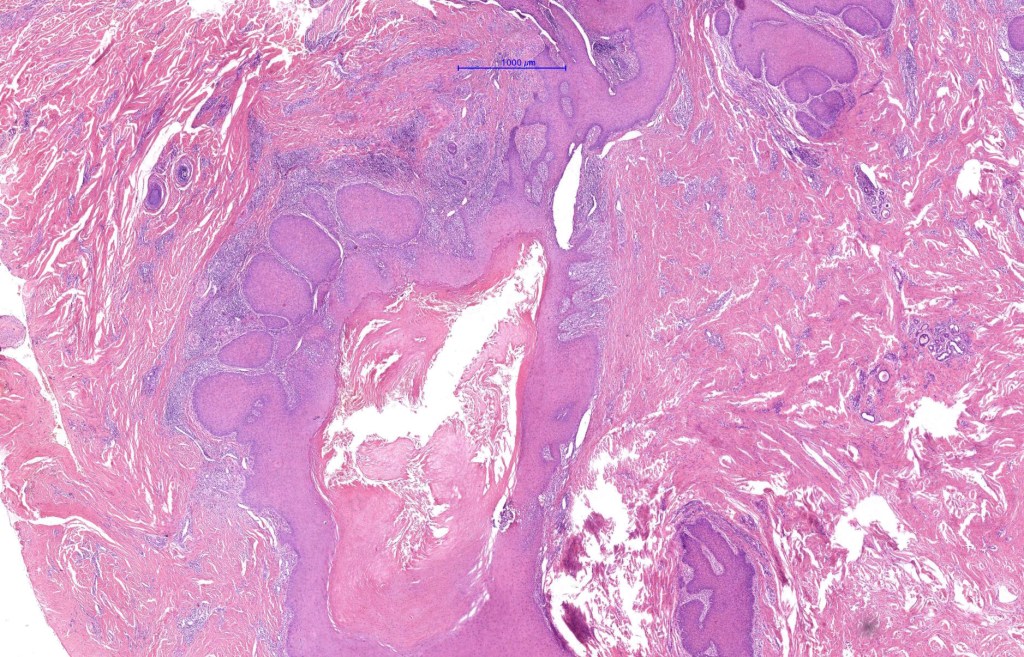

Histological features

•Multilobulated cyst with associated lobules of well differentiated squamous epithelium

•PAS+ve cytoplasmic vacuolation indicating outer root sheath differentiation

•+/- peripheral palisading

•No pleomorphism or significant mitotic activity

•Eosinophilic basement membrane

•Infundibular>trichilemmal keratinization